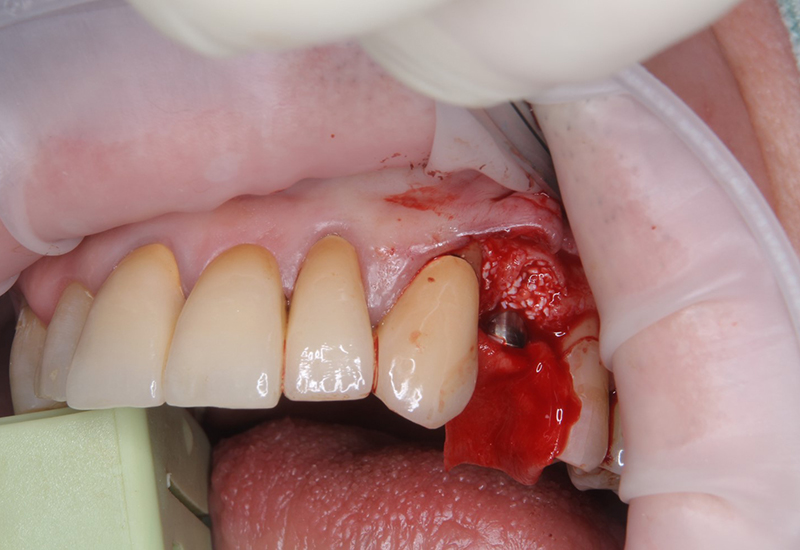

治療後 |